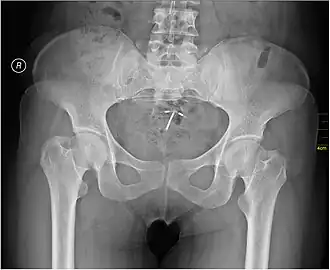

Het spiraaltje is een voorwerp dat in de baarmoeder-holte wordt gebracht om een zwangerschap te voorkomen. Een spiraaltje wordt ook wel een IUD genoemd. Dit staat voor intra-uterine (in de baarmoeder) device. De anticonceptiespiraal is al jaren een van de meest betrouwbare effectieve, goedkope en meest gebruikte vormen van langetermijnanticonceptie.

Inbrengen en verwijderen van het spiraaltje wordt gedaan door een huisarts, een gynaecoloog of een gecertificeerde verloskundige. Als een vrouw zwanger is geweest kan ze vanaf 10 tot 12 weken na de bevalling een spiraal laten plaatsen. Zes weken na plaatsing van het spiraaltje wordt er vaak een controle gedaan of de spiraal op de juiste plaats in de baarmoeder zit.